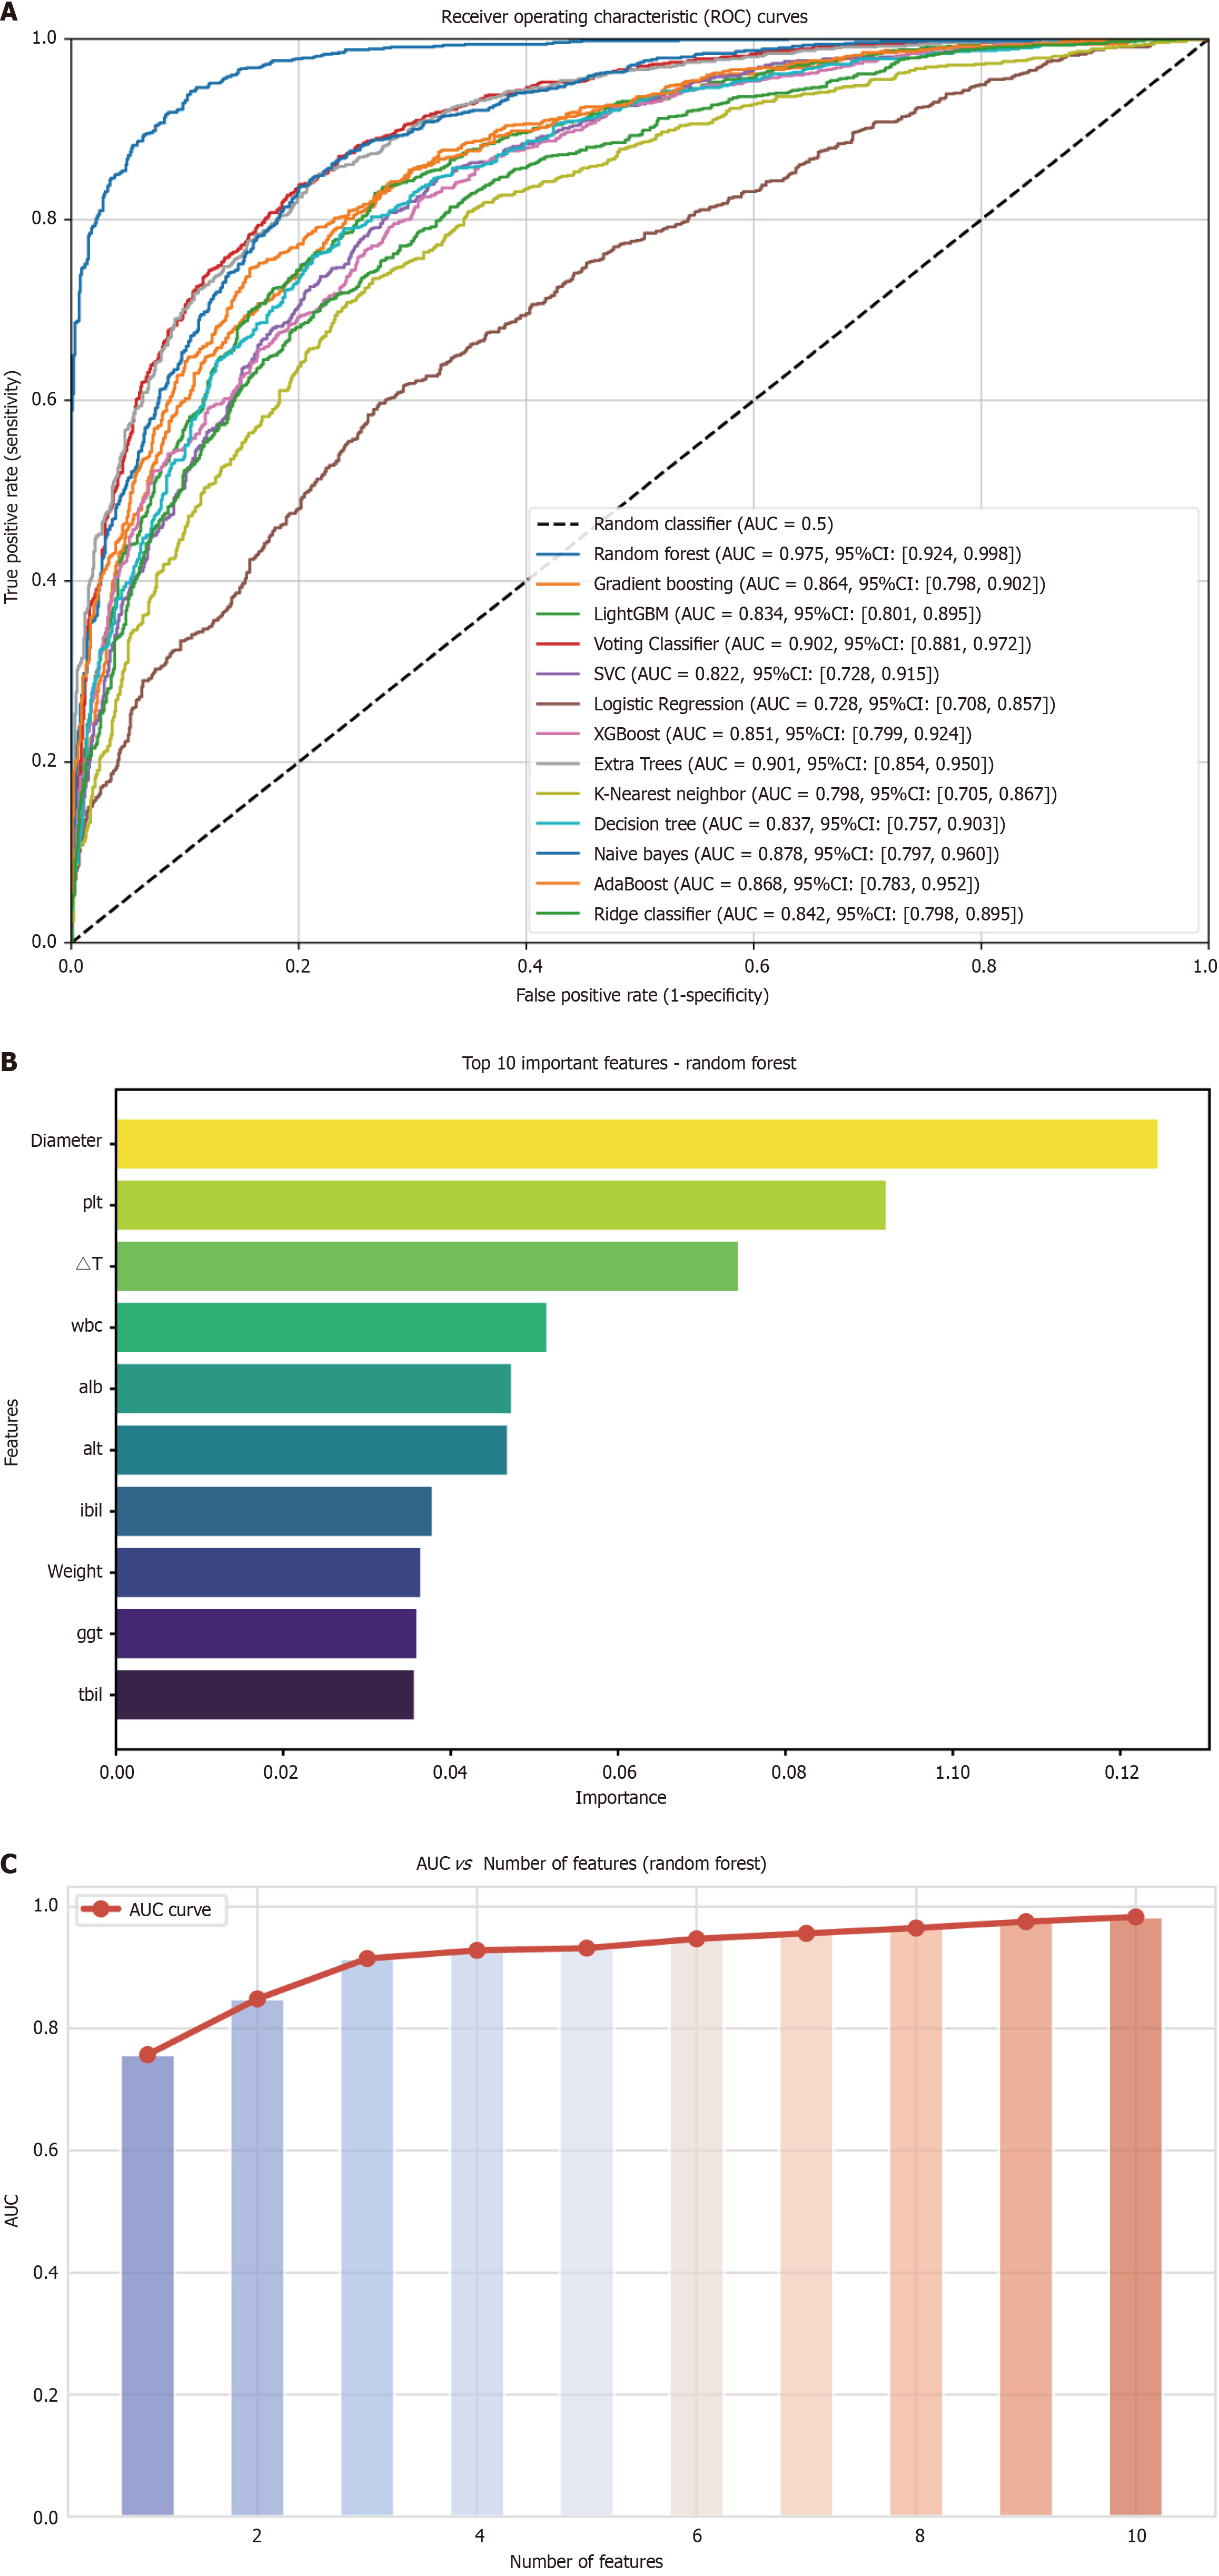

Figure 3 Analysis of variable importance and its correlation with area under the curve.

A: Receiver operating characteristic curves of different machine learning models in the internal validation cohort; B: The top ten most important variables, ranked by their contribution to the model; C: Area under the curve values corresponding to varying numbers of selected variables. A peak area under the curve is observed with four variables. AUC: Area under the curve; CI: Confidence interval; PLT: Platelet count; WBC: White blood cell count; ALB: Albumin; ALT: Alanine aminotransferase; IBIL: Indirect bilirubin; GGT: Gamma-glutamyl transferase; TBIL: Total bilirubin.